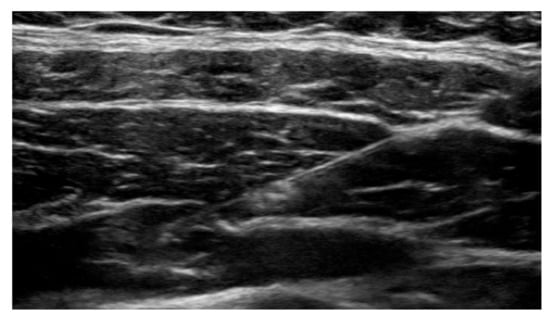

Anesthesiologists specializing in regional anesthesia, used an ultrasound guided 21-gauge needle to access the transversus abdominis plane. Once the position was confirmed, liposomal bupivacaine was administered, and appropriate spread of the medication was monitored and confirmed in real time. Ultrasound images of critical points were stored in the patient’s chart for future reference (Figure 1).

The ultrasound image depicts a 21-gauge, 4 inch needle containing liposomal bupivacaine in the transversus abdominis plane adjacent to the nerve plexus.

Figure 1. Ultrasound guided transversus abdominis plane block.